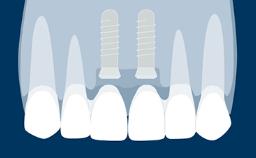

Structured Assessment and Treatment Planning

Discolored Central Incisor

Learning Module